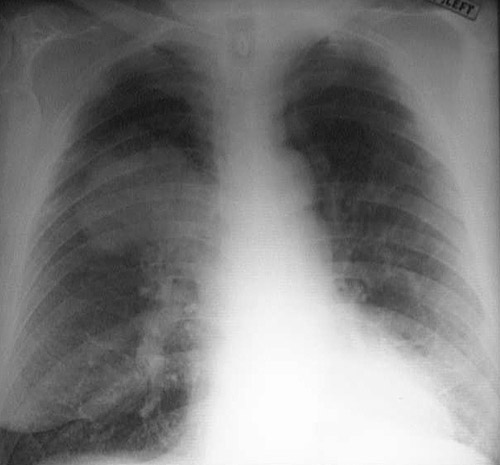

Click on the bronchogenic carcinoma in the chest radiograph above:

This chest radiograph demonstrates a large squamous cell carcinoma of the right upper lobe.